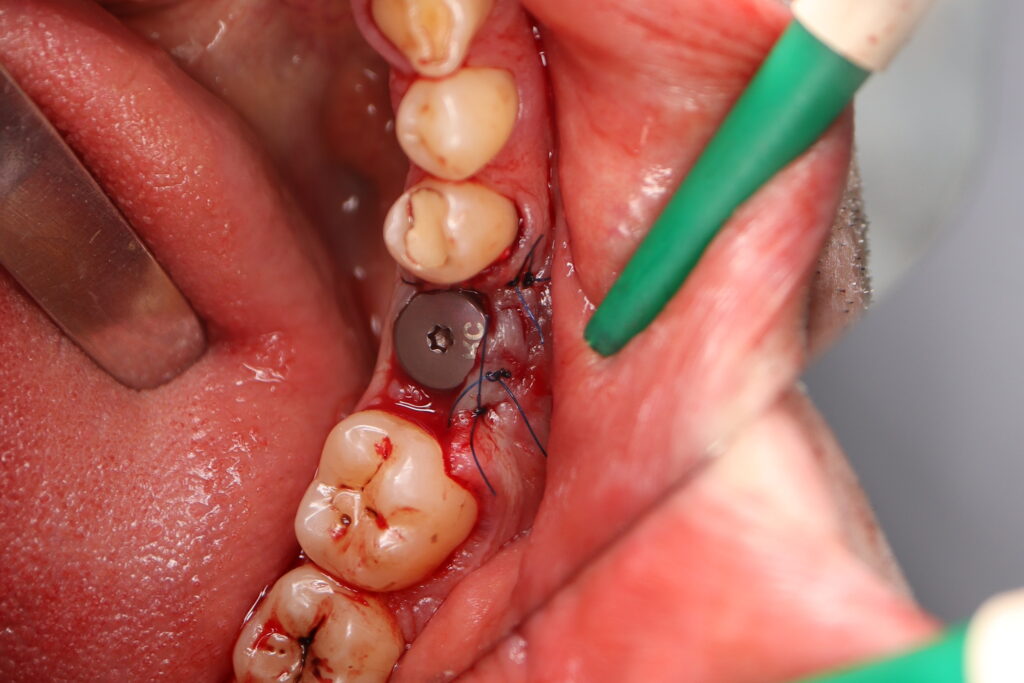

хирургический этап

Это фото может содержать тяжелый для восприятия контент

Были установлены 4 имплантата Straumann BLT. На верхней челюсти в области зуба 2.1 в одно посещение был установлен имплантат и изготовлена временная коронка.

Также в данной области выполнена пластика десны.